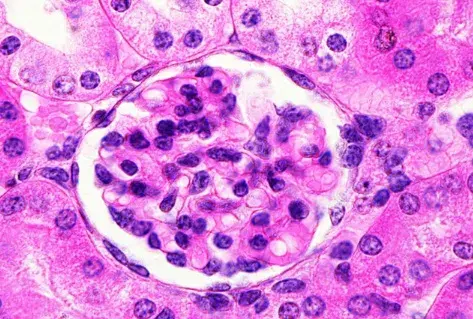

Nefropatía Membranosa: ¿Y si el paciente no responde al tratamiento inicial?

Nefropatía Membranosa: ¿Y si el paciente no responde al tratamiento inicial?

En este video, abordamos estrategias para tratar a pacientes con nefropatía membranosa que no responden al tratamiento inicial. Se enfatiza la importancia de la reevaluación constante y del ajuste del régimen de tratamiento en función de los resultados y del estado del paciente.

Cómo tratar la Nefropatía Membranosa de manera práctica

Cómo tratar la Nefropatía Membranosa de manera práctica